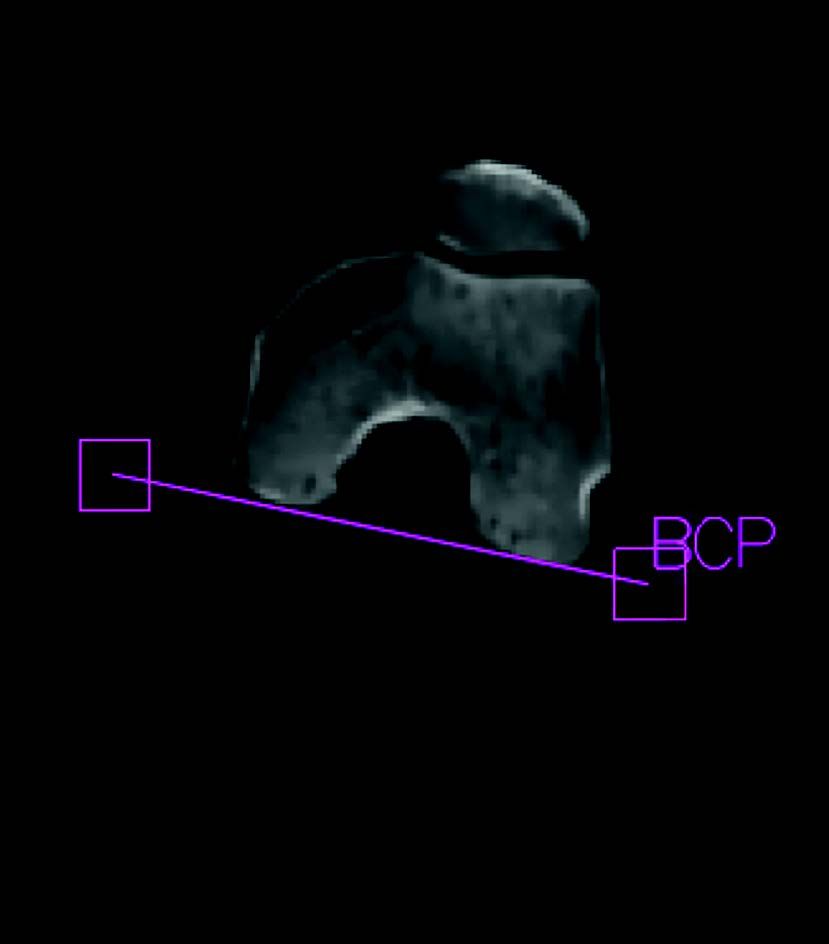

Step 5: femur position: the software measures the posterior bicondylar line then defines a femur from the front and side on (Fig. 5). The greater trochanter, the digital fossa and the lesser trochanter landmarks can thus be specified. All of these measures are used to define the femoral torsion and offset.

Step 1: The frontal and side on scout view can be used to perform length measurements outside and within the joint (Fig. 2).